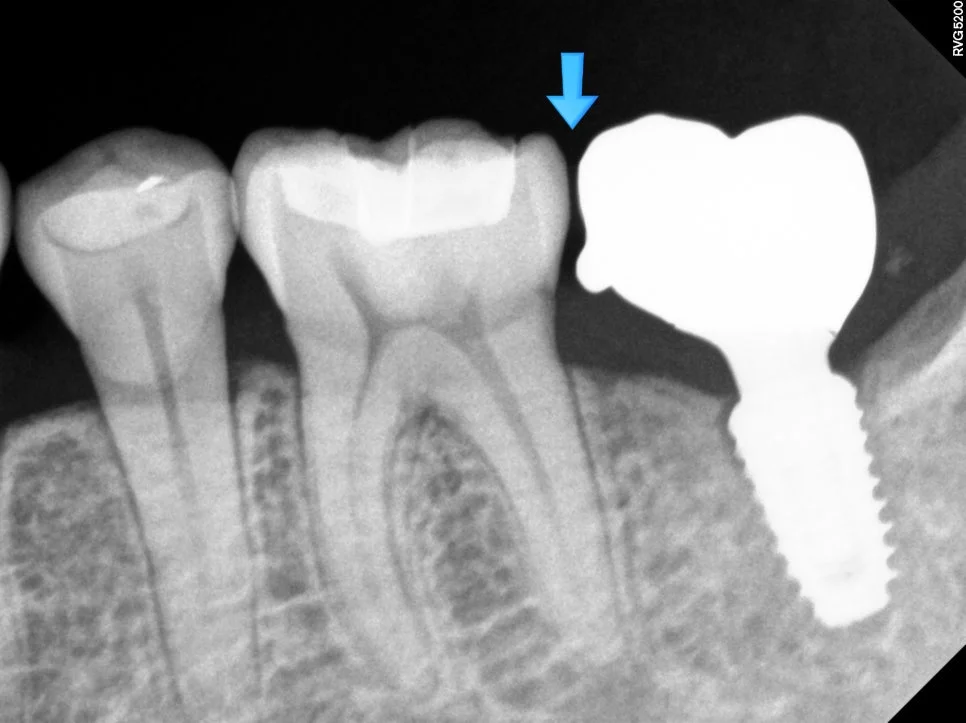

임플란트 틈새 진단 방사선 사진

X-ray에서 임플란트와 치아 사이 틈 확인

임플란트 기둥 크라운 재제작 과정

임플란트 뿌리는 그대로, 기둥과 크라운만 재제작

사진을 찍어보면 명확하게 임플란트와 치아 사이에 틈이 보이는데요. 이 정도 공간이면 음식물이 정말 엄청나게 끼게 됩니다ㅜ

음식물이 끼는 사이 틈에는 충치/잇몸질환이 둘 다 잘 생기게 되므로 음식물 끼임은 그 자체로 문제입니다ㅜ